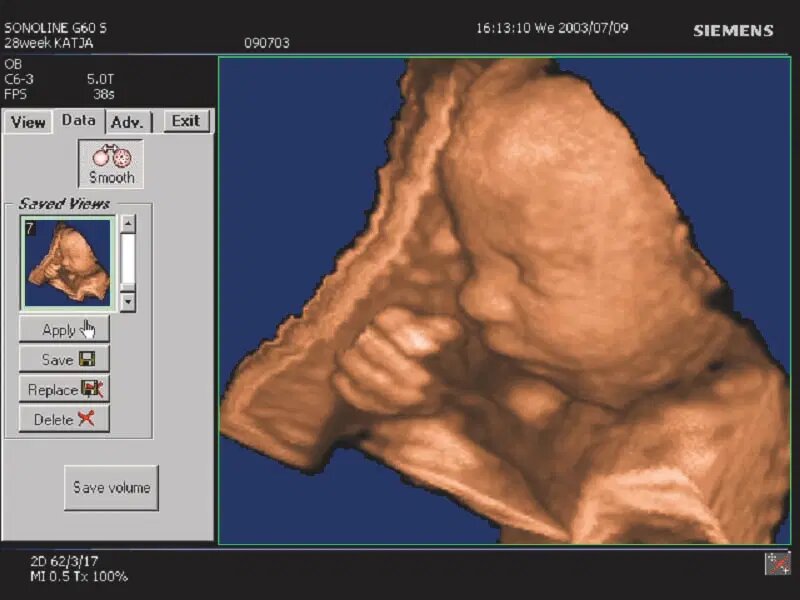

۱۹۹۹

نرمافزار "۳-Scape Real-Time ۳D" اولین نرمافزار زمان واقعی سه بعدی با وضوح بالا؛ که اجازه پردازش و نمایش تصاویر سه بعدی از ویژگیهای آناتومیک را فراهم میساخت. این امر در سونوگرافی جنین بسیار مفید است، زیرا حرکات جنین معمولاً مانع تشخیص دقیق میشود.